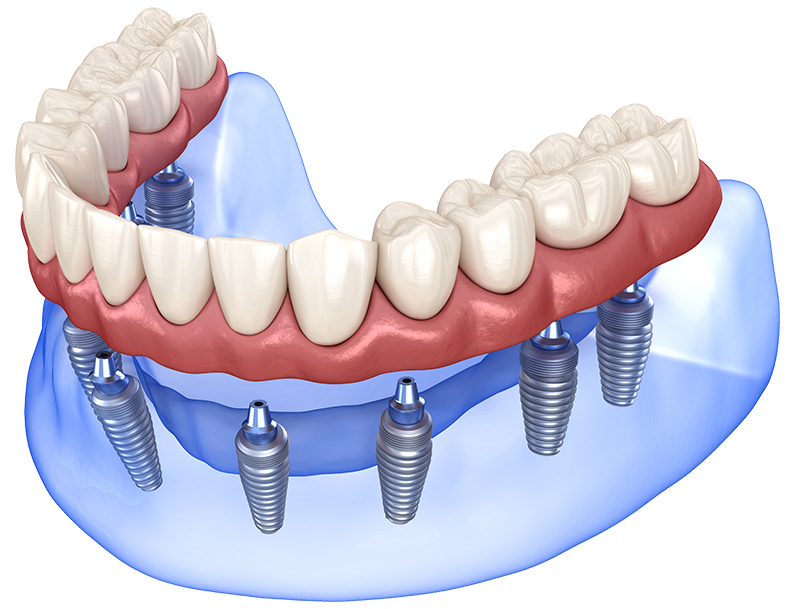

전체 임플란트

충치, 잇몸질환, 사고 등의 이유로

치아가 전부 상실된 경우

고정식으로 치아를 모두 재현하는 시술로 기능 회복 뿐만 아니라

전반적인 상황을 고려해야 하므로 경험이 많은 시술자에게 받아야 합니다.

implant_con09_01

• 고정

씹는 힘으로

임플란트가 움직이지 않게

고정

• 연결

식립한 임플란트와

보철물이 어긋나지 않게

정밀한 연결

• 분산

힘이 한 군데로

쏠리지 않도록 구조적으로

하중 분산

• 교합

주변 치아의 적절한 조화를

위해 힘의 균형을 맞추도록

조정